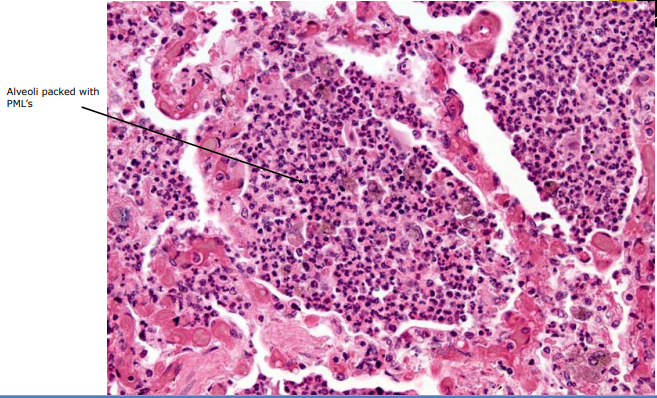

Diseases of the LRT - Pneumonia

A

Due to an infection of the alveoli caused by several types of bacterial or viral pathogens

Tissue fluids accumulate in the alveoli reducing the surface area exposed to air

Bronchiolitis - demonstrates exudation of PML’s into the adjacent alveoli